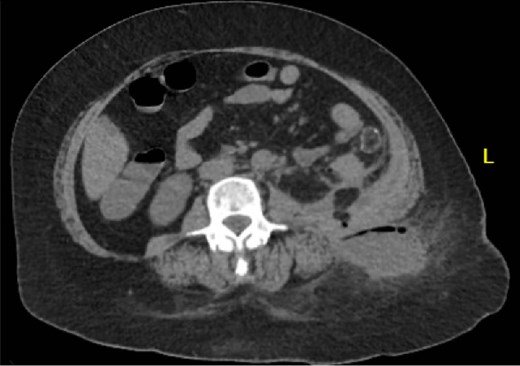

A 64 year old female with a history of recent diverticulitis treated with outpatient antibiotics and a fall two months prior to her left flank presented to the hospital with persistent left flank and abdominal pain. Initial workup showed a left flank fluid collection that connected to the left psoas muscle and retroperitoneum with associated descending/sigmoid diverticulosis (Fig. 1). The patient was admitted, started on empiric IV antibiotics, and an IR-guided drain was placed into the subcutaneous abscess. A repeat computed tomography (CT) scan done with rectal contrast showed a colocutaneous fistula to the descending/sigmoid colon in the area of the previous abscess. Therefore the patient was taken to the operating room on hospital day two. Intra-operatively, the patient was found to have purulent peritonitis, left colon diverticulitis, a colocutaneous fistula, and an associated pericolic abscess. The patient underwent extensive lysis of adhesions, take down of fistulous tract, and left colectomy with primary anastomosis. The fascia was closed with #1 non looped PDS and interrupted figure of eight stitches. The umbilicus was reapproximated with sutures and a negative pressure subcutaneous wound vac was placed to the midline laparotomy incision and kept on continuous suction at -125mmhg. The first wound vac change occurred on postoperative day (POD) 3 (Fig. 2a) and then the wound vac was changed every other day in the hospital until a layer of granulation tissue was formed along the entire incision. On POD 13, DPC was performed by reapproximating the skin edges with staples (Fig. 2b). The patient’s hospital course was complicated by a prolonged postoperative ileus requiring supplemental total parenteral nutrition (TPN). The patient was discharged to home on POD 13 tolerating a diet and with one week of oral antibiotics. The patient was then seen in the office 15 days after discharge and DPC on POD 28. The midline incision was closed, healing well, and was without any signs of SSI (Fig. 2c).

Patient A. Initial CT abdomen and pelvis showing left subcutaneous fluid collection extending intra-abdominally.